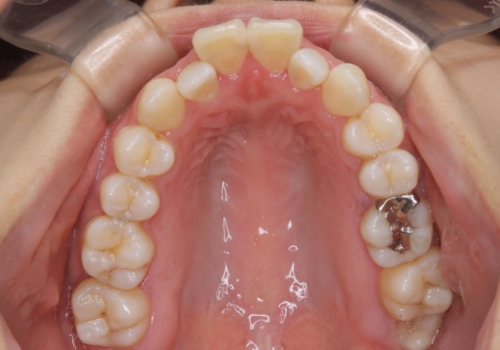

マイクロインプラントについて

インビザライン治療では奥歯の圧下が問題なく行えますが、ワイヤー治療ではマイクロインプラントを使用しなければ奥歯の圧下を行うことが難しいです。